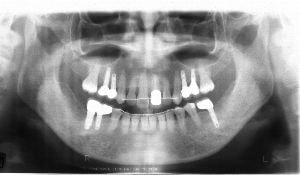

治療例2 (補綴処置+矯正)